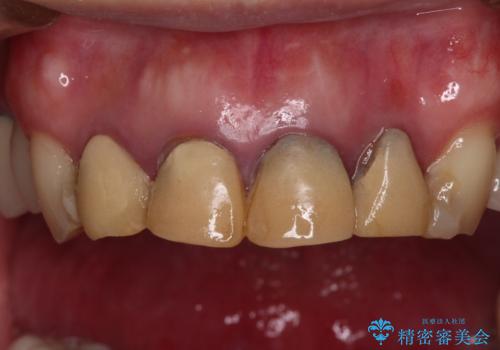

- 仮歯装着後に放置してしまい、恥ずかしいとのことで来院された患者様です。

仮歯が不適合で歯肉が腫脹していたため、しっかりと調整した新しい仮歯にして腫れを改善した上で、オールセラミッククラウンにて補綴することとしました。